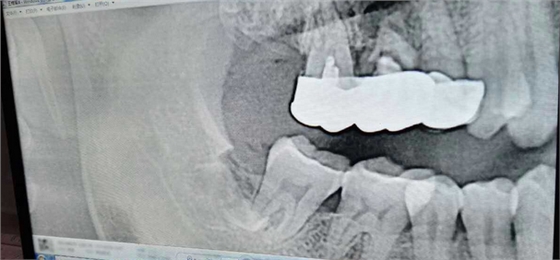

病例:患者男性47歲

右下8骨埋伏并且黏連;從根分叉處通過;有彈性;術(shù)中看到神經(jīng)束

實在找不到;近中牙冠沒去干凈

像這種不切除的牙冠,以后吸收的可能性不是很大,但有排除的可能性,自己自行排出,要是牙根的話吸收的可能性比較大

像這種沒有癥狀的殘留牙體組織不用去除可以吧